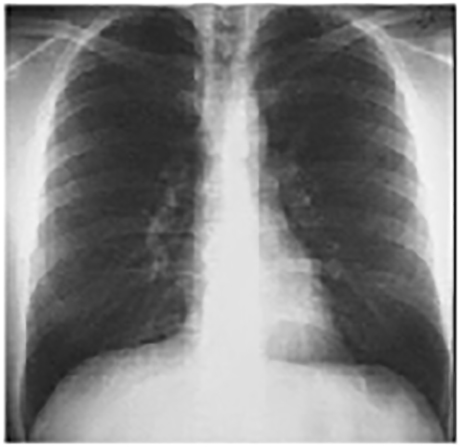

You are incorrect - the best interpretation of the chest X rays in our patient is right ventricular enlargement + dilated pulmonary trunk + increased pulmonary vascularity.

These chest X rays are normal. The PA view demonstrates no abnormalities of the bone structures, lung fields, or cardiac silhouette. The right and left heart borders are normal as are the great vessels superior to the cardiac silhouette. Note the cardiothoracic ratio is also normal, that is, it is less than 50%.

The lateral view is normal, with no evidence of chamber enlargement including the normal anterior shadow of the right ventricle and posteroinferior shadow of the left ventricle.